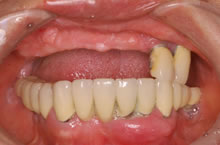

【2】治療前写真2

他院で3年前に上アゴ全体にインプラント6本を入れその上に固定性入れ歯を装着されておりましたが、経過不良に伴い1年経たずに2本以外は抜け落ちたため、事後の改善と再治療を希望され受診されました。どうしても義歯ではなく、インプラント治療を行い満足行く楽しい食生活をしたいとのご希望でした。

残りのインプラント2本も揺れていました。 CT検査の結果により、左右上奥のインプラントを支える骨が不足していました。そのため、揺れているインプラント撤去と同時に、支えるの骨を増やす特殊な手術、上顎洞底挙上術(サイナスリフト)を併用し、じっくり治療していけばインプラント治療が可能になることを説明しました。ご本人も術後の回復された後の状態がイメージでき、治療を希望され開始しました。 現在、丈夫な骨を再建する特殊な治療もインプラント6本を埋入終了し、仮歯を装着して美味しく食事をされています。 今後、下アゴにも15年以上前に入れてご自分の歯と連結されていますが揺れている経過が危ういインプラントがあるため、撤去し、再度、インプラントを予定しています。